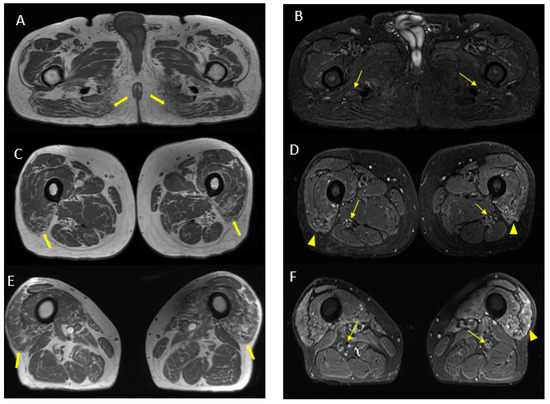

Figure 9.

Pathological alterations of the left sciatic nerve (thin arrows in (B,D)), characterized by a significant increase in volume (CSA in the upper third of the thigh of about 123 mm2) with associated fascicular hypertrophy and an increase in signals in T2w images, especially in the height of the middle and lower third of the thigh and with extension to the tibial nerve (thin arrow in (F)), up to the lower third of the leg. Also, in the right sciatic nerve, there are some alterations (thin arrows in (B,D), much more tenuous than the contralateral nerve, characterized by an increase in the thickness of the nerve (CSA at the upper third of the thigh of about 110 mm2), a moderate increase signal in T2w images and fascicular hypertrophy, without evident tibial nerve signal alterations. Mixed denervation, acute and chronic, of left and right semimembranosus and posteromedial compartment muscles of the left leg (muscle hyperintensity and fascial edema in STIR, thick arrows in (D,F)) and fat replacement (muscle bundle atrophy with replacement of hyperintense tissue at T1W in (A,C,E), more evident in some areas: arrowheads in (C,E)).

MR findings: increase in thickness and signal intensity in T2 W images of lumbar and sacral roots, particularly in the left S1 root that appears to be pathological (Figure 8). Pathological alterations of the left sciatic nerve, characterized by a significant increase in volume with associated fascicular hypertrophy and an increase in signals in the T2w images, especially at the middle and lower thigh and extending in the leg to the tibial nerve. An increase in nerve thickness, a moderate signal increase on T2w images, and fascicular hypertrophy without evident alterations of the tibial nerve signal characterized initial and subtle alterations in the right sciatic nerve. Signs of acute and chronic muscle denervation in the left leg and thigh and initials in the right leg (Figure 9).

Nerve ultrasound findings: diffuse hypertrophy of the left sciatic nerve (maximum cross-sectional area 110 mm2 vs. 80 of the contralateral nerve) and of the tibial nerve at the popliteal level.

Interpretation: MR neurography study confirmed left sciatic and tibial nerve pathology; however, it also showed alterations of the lumbo-sacral plexus and initial involvement of the right sciatic nerve, suggesting a condition of polyradiculoneuropathy. In the light of MR and clinical data, a diagnosis of loco-regional variant CIDP was made. CSF analysis confirmed an increased protein level.